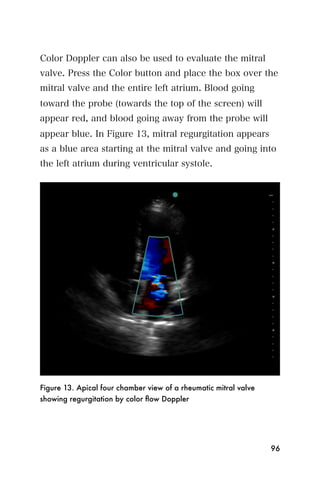

Color Doppler can also be used to evaluate the mitral

valve. Press the Color button and place the box over the

mitral valve and the entire left atrium. Blood going

toward the probe (towards the top of the screen) will

appear red, and blood going away from the probe will

appear blue. In Figure 13, mitral regurgitation appears

as a blue area starting at the mitral valve and going into

the left atrium during ventricular systole.

Figure 13. Apical four chamber view of a rheumatic mitral valve

showing regurgitation by color flow Doppler